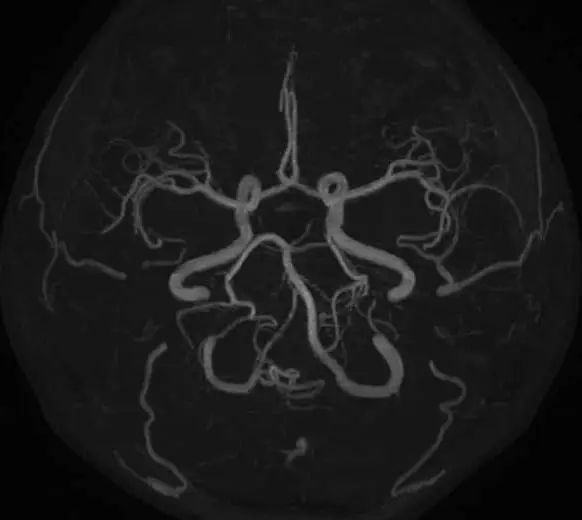

- 頭頸部領域、脳潅流イメージング(ASL)など